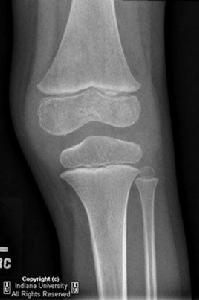

影像學

早期可見關節附近軟組織腫脹,骨骺部骨質稀疏。晚期嚴重關節炎患者可見骨表面破壞,關節腔變窄,骨囊性變,骨膜反應及關節半脫位等。